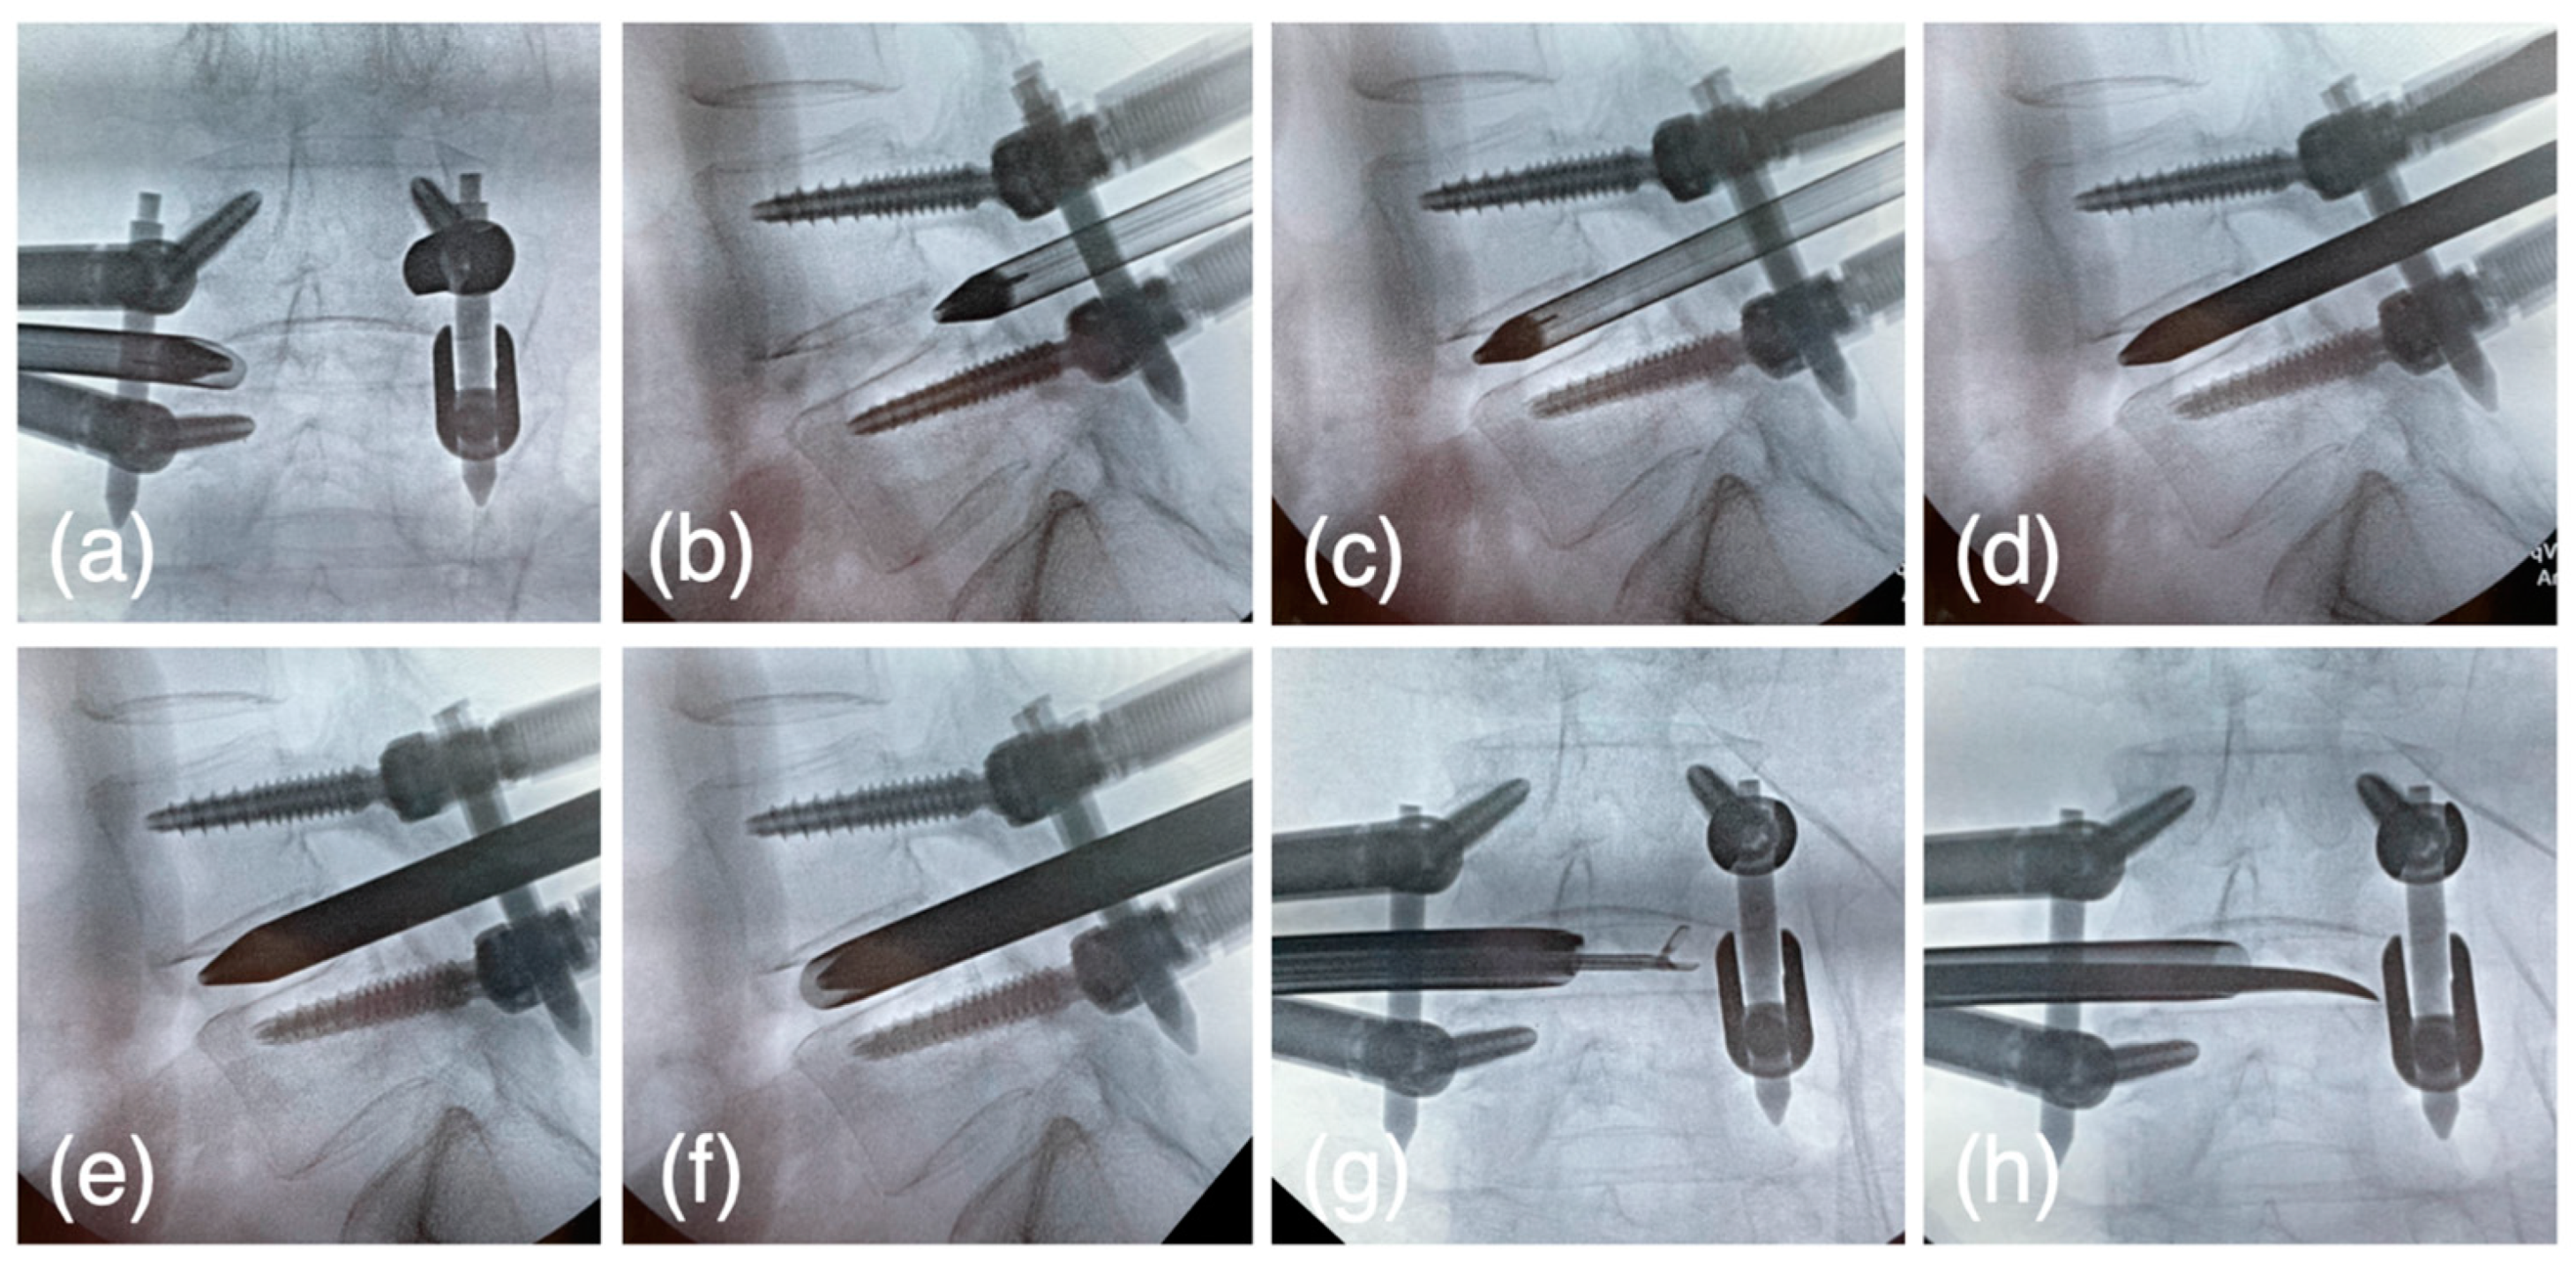

Figure 5.

(a,b) The pencil dilator is inserted after the tip of the cannula reaches the medial line of the pedicle w/wo enlargement of the foramen. (c) 1st step: Loosen the set screw and drive the pencil dilator into the disc space. (d) Tighten the set screw and change to the oval dilator. (e) 2nd step: Loosen the set screw, 90° rotate the oval dilator to acquire the disc height. (f) 3rd step: Tighten the set screw and reverse the dilator, then insert the oval cannula over the dilator. Finally, loosen the set screw and the dilator is rotated with the cannula, and the disc height is expanded (g,h). The disc curettage was performed through the sleeve fluoroscopically or endoscopically using dedicated forceps and a Cobb elevator.

2.5.5. The First Step for Acquiring the Disc Height

At this point, the tip of the dilator is supposed to locate at the posterior intervertebral disc and medial line of the pedicle. The cranial set screws were freed, and the dilator was hammered into the disc space at an angle of 45° from a horizontal line. (Figure 5c) Expansion of the disc height was observed during the dilator insertion into the disc space, and the set screws were tightened to maintain the acquired disc height.

2.5.6. The Second Step for Acquiring the Disc Height

The oval dilator (9 × 7 mm), oval sleeve (10.6 × 9 mm), U-shaped oval sleeve, dedicated cobb elevator, ring curette, and J-shaped nerve retractors (Japan Medical Dynamic Marketing, Tokyo, Japan) were newly developed or updated and used from this step. The pencil dilator was removed, and the oval dilator was inserted through the same passage with a short axis craniocaudally. (Figure 5d) The cranial set screws were freed, and the oval dilator was rotated 90 degrees, so that further expansion of the disc height was acquired with the long axis craniocaudally (Figure 5e). Set screws were tightened to maintain the disc height.

2.5.7. The Third Step for Acquiring the Disc Height

The oval dilator was rotated and the short axis was set craniocaudally. The oval sleeve was then inserted over the oval dilator. The cranial or caudal set screws were freed, and the oval dilator was rotated 90 degrees; that final expansion of the disc height was acquired with long axis craniocaudally (Figure 5f). Set screws were tightened to maintain the disc height. Theoretically, after the third step the disc height increased by at least 10.6 mm.